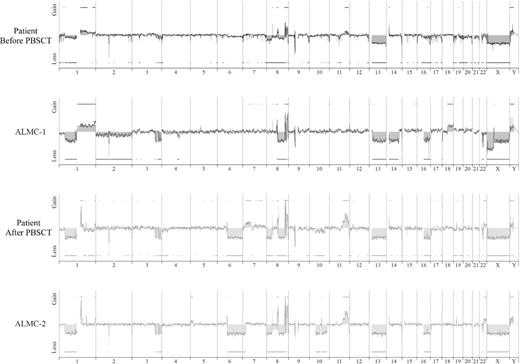

Array CGH analysis

We next used array CGH, a methodology that permits a much higher resolution map of the 4 genomes than that achieved by conventional methods (Figure 4), to test the genetic relationship between the cell lines and the primary patient cells. This analysis permits 2 major conclusions. First, the data clearly demonstrate the overall similarity between the cell lines and the patient primary cells. Second, a number of genetic changes were acquired during the course of disease progression, including regional chromosomal gains in 1q, 11q, and 22q, and losses in 6q, 8p, 10p, and 10q, several of which have been associated with poor prognosis myeloma (reviewed by Tonon30 ). Of interest, 6q deletion is frequently observed in Waldenstrom macroglobulinemia and is associated with features of adverse prognosis.31

Genome-wide high resolution aCGH. Chromosomal copy number alterations across the pre-PBSCT, ALMC-1, post-PBSCT, and ALMC-2 cells are plotted for each probe evenly aligned along the x-axis in chromosomal order.

Although it is beyond the scope of this report to present a detailed analysis of all gains and losses, Figure 5 presents a more detailed view of chromosomes 1, 3, 8, and 22. Chromosome 1q21 is amplified only in the primary patient cells post-PBSCT and the ALMC-2 line. This region has a number of interesting genes that have been shown to play a role in other cancers, including the transcription factor, Arnt32 ; the Bcl2 family member, Mcl133 ; the micro RNA, MIRN55434 ; FLG2, a member of a family of genes whose products interact with intermediate filaments35,36 ; and the DNA-binding histone protein, HIST2H2AB.37 Several regions on chromosome 3 have undergone losses in all 4 samples tested and include ABCC5, a multidrug resistance gene,38 and ATP13A5, a lipid-transporting p-type ATPase.39 The transcription factor, TRMT12 (chromosome 8), has been shown to be amplified in breast carcinoma40 and is amplified in both primary patient samples and both cell lines (Figure 5). Finally, losses were also observed on chromosome 22 in all 4 samples. One of these regions includes the IGL locus and probably reflects genomic DNA lost on chromosome 22 during VJ rearrangement. Consistent with λLC expression, there is a biallelic loss of the κLC locus on chromosome 2p12 in all 4 samples studied (Figure 4). The second region of chromosome 22 loss highlighted involves the NF-2 gene, a known tumor suppressor gene.41,42 Collectively, these data demonstrate how closely the in vitro passaged cell lines resemble the primary patient cells. This analysis also demonstrates how the cell line established from the diagnostic marrow similarly evolved, albeit in vitro, in a way that largely mirrored in vivo evolution of the primary tumor.